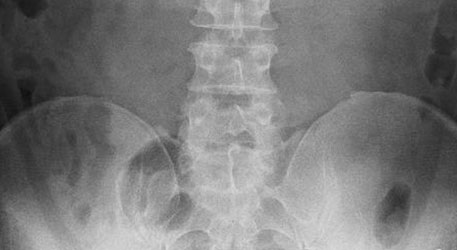

みなさんの中にも今まで、病院などでレントゲンをとって「骨には異常がない」と言われ原因を特定されず、湿布と痛み止めをもらっただけという方も多いのではないでしょうか?

しかし、近年では、78%の腰痛は原因が特定できると言われています。

当然、原因が不明なぎっくり腰や腰痛では治療のしようがありませんが、原因が特定さえされていればスムーズな改善も期待できるということです。

ある研究で、「腰椎のない人にどれくらい腰の異常があるか」調べたものがあります。

その結果は

- 痛みが無いにも関わらず、椎間板ヘルニアは76%に存在する

- 痛みが無いにも関わらず、椎間板の変性は85%に存在する

というものでした。

つまり、ぎっくり腰を起こしてMRIなどで検査をした結果「椎間板ヘルニアがある」ことが分かったとしても、それがぎっくり腰とはなんら関係がない場合がある、ということを示しています。

それにも関わらず

「ぎっくり腰の原因は椎間板ヘルニア」

だとして治療を進めてしまうことで、 誤った治療を続けてしまうことになり、それはもちろん、改善を遅らせてしまう原因になってしまいます。